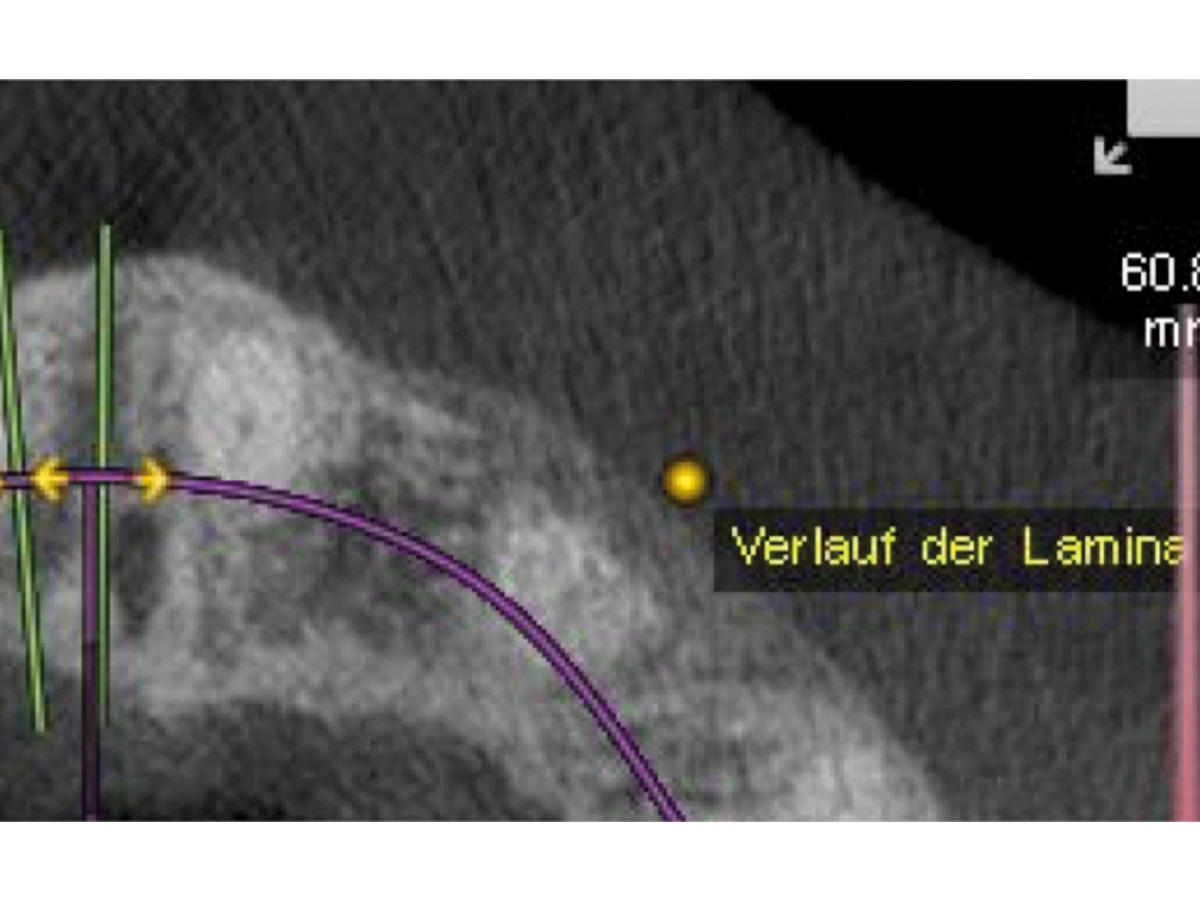

DVT mit Pins nach 6 Monaten.

Abbildung 17

Verlauf der OsteoBiol Lamina.

Abbildung 18

Kontroll-DVT nach 6 Monaten.